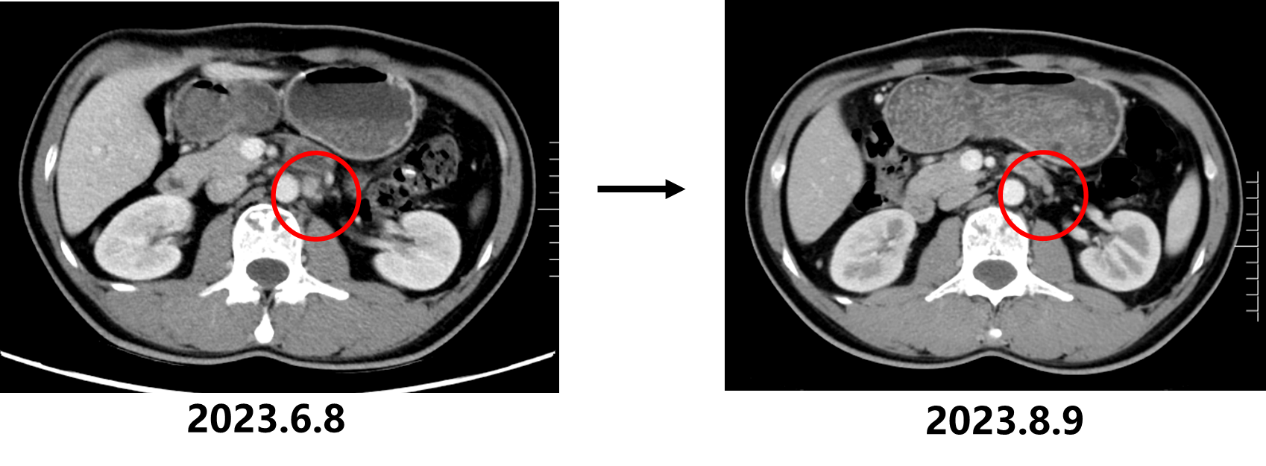

2023.6.8 胸腹部+盆腔CT:1. 胃底贲门部胃壁增厚,考虑胃底贲门癌,并肝胃间隙及腹膜后多发淋巴结转移瘤(大者短径20mm)、双肺多发转移瘤可能性大(大者长径6mm);2. 左侧髂骨、右侧坐骨及骶骨高密度影,考虑骨岛或骨转移瘤。

• 2023.8.10复查CT:胃底贲门部胃壁增厚明显改善,肝胃间隙及腹膜后多发淋巴结转移瘤较前缩小(大者短径17mm)、双肺多发转移瘤较前缩小、减少,疗效评估为部分缓解(PR)。